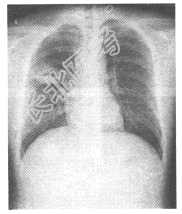

- [材料题] 某患者,女,38岁,以右下肢挤压伤入院,3日前突发高热、寒战、咳嗽,血WBC2.0×109/L,胸片如图:

- 多项选择题1.则以下最可能的诊断为

F、急性肺脓肿